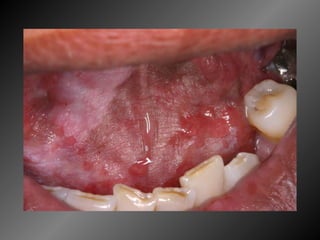

Granuloma Piogênico Lesão Nodular Séssil ou pediculada Avermelhada ou vinhosa Sangramento espontâneo e áreas de micro-ulceração superficial

Granuloma Piogênico Lesões nodulares de coloração avermelhada ou vinhosa Provavelmente uma reação inflamatória exagerada ao trauma menor Crescimento rápido, às vezes sangramento espontâneo Ocorre em qualquer idade mas parece mais freqüente em adultos jovens e adolescentes  Localização mais comum: gengiva (NEVILLE,2001)

Granuloma Piogênico Lesões mais antigas, são menos vasculares e mais fibrosas Papila interdental e regiões anteriores são áreas preferenciais, principalmente por vestibular (BORK,1996)

25 - L.C.S., sexo masculino, 18 anos de idade, se apresentou com queixa de aumento de volume na gengiva entre os dentes 23 e 24. Pelo exame clínico, constatamos a presença de um nódulo séssil, de contornos irregulares, coloração avermelhada, com sangramento abundante ao mínimo toque e evolução de 1 ano. O paciente apresentava higiene bucal precária com presença de placa bacteriana e tártaro. Com base no quadro clínico, o diagnóstico é: a) Fibroma e granuloma piogênico. b) Granuloma piogênico e hiperplasia fibrosa inflamatória. c) Lesão periférica (granuloma) de células gigantes e fibroma. d) Granuloma piogênico e lesão periférica (granuloma) de células gigantes. e) Hiperplasia fibrosa inflamatória e fibroma.

Granuloma Piogênico LesãoNodular Séssil ou pediculada Avermelhada ou vinhosa Sangramento espontâneo e áreas de micro-ulceração superficial

Granuloma Piogênico Lesõesnodulares de coloração avermelhada ou vinhosa Provavelmente uma reação inflamatória exagerada ao trauma menor Crescimento rápido, às vezes sangramento espontâneo Ocorre em qualquer idade mas parece mais freqüente em adultos jovens e adolescentes Localização mais comum: gengiva (NEVILLE,2001)

Granuloma Piogênico Lesõesmais antigas, são menos vasculares e mais fibrosas Papila interdental e regiões anteriores são áreas preferenciais, principalmente por vestibular (BORK,1996)